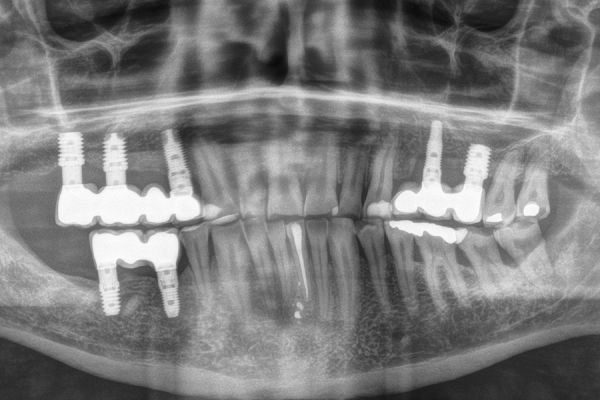

Queridos compañeros y lectores de Científica Dental, En este número de primavera de la revista os ofrecemos siete trabajos que esperamos sean de vuestro interés. Contamos con cuatro artículos originales, dos casos clínicos y una revisión de la literatura, que abarcan diferentes áreas de la actividad y actualidad científica de nuestra profesión. Anitua analiza en un interesante trabajo la relación entre las fracturas protésicas implantológicas y la apnea del sueño, así como el tratamiento a través de un dispositivo de avance mandibular. El trabajo de Sánchez-Fernández y cols. realiza un magnífico estudio sobre las manifestaciones orales del COVID leve hasta el persistente.

El equipo de Jiménez-Pascual y cols. a través de una actualizada revisión bibliográfica presenta los nuevos avances en la revitalización pulpar en dientes inmaduros. A continuación, se presentan dos casos clínicos. El primero de Beca y cols. analiza el comportamiento clínico, radiográfico e histomorfométrico del diente autólogo en la elevación de seno maxilar lateral de acceso lateral, acompañado de unas imágenes de la técnica y seguimiento de seis meses. Sánchez-Ruiz y cols. analizan el tratamiento quirúrgico de la patología pseudoquística sinusal a través de un caso clínico donde recogen las imágenes del diagnóstico, tratamiento y resolución a los seis meses.